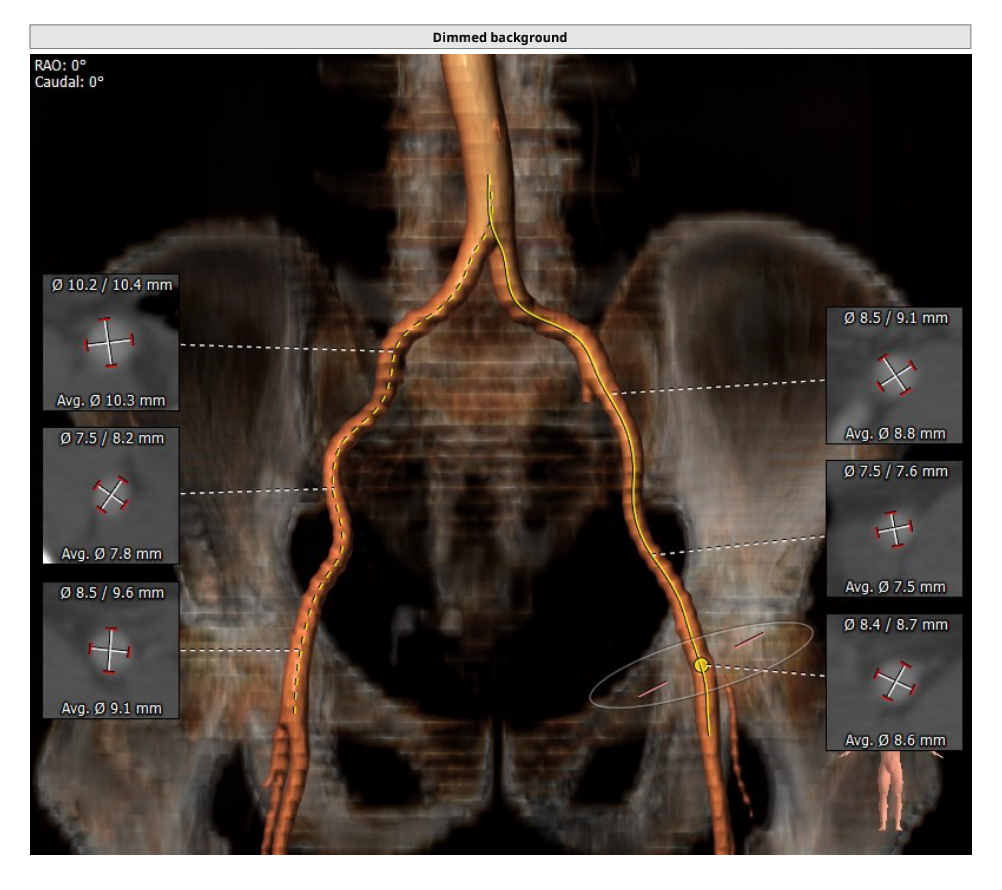

入路情况